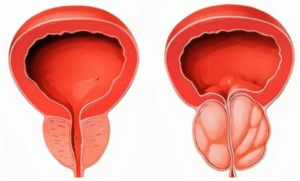

- Ressecção Transuretral da Próstata (RTU):

- Procedimento minimamente invasivo para remover tecido prostático obstrutivo.

- Enucleação Prostática

- Procedimento cirúrgico minimamente invasivo para remover o tecido prostático obstrutivo e melhorar o fluxo urinário.